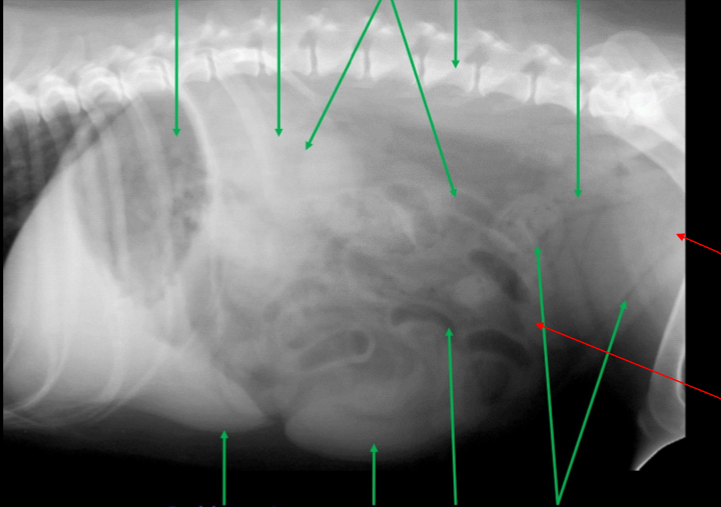

Identify the kidneys and bladder

Label the kidneys and bladder

A